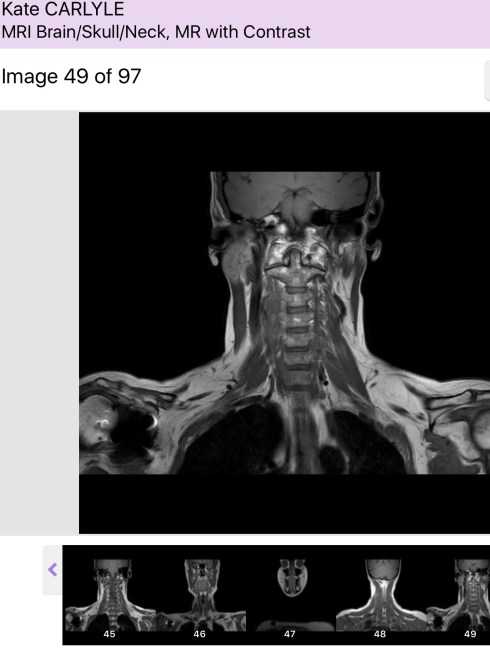

I truly believe that, which is why I’m not completely terrified of a ‘suspicious mass’ recently discovered in my mouth.

It’s coming out in a few days time. The surgeon is highly experienced and during the necessary scans and tests of late has become a good fit in my (now rather extensive) care team.

Whilst acknowledging if this case were for his surgical exam, he would leave things for a few months, he duly pointed out that this is real life and this patient has a nasty cancer history. So, we agreed that after observing for a set period – the ‘watch and wait’ approach is clearly not in my best interests.

This may turn out to be a sublingual gland that is just ‘misbehaving’ given my overall health. Fingers crossed. If it is however, another hit of the ‘Big C’, I’ll deal with it as I have the last three.

Fortunately they won’t have to go through my face (or brain! I was shocked when he mentioned casually that sometimes that is the best/only way to get to the area), they’ll go into the floor of my mouth, through my mouth.